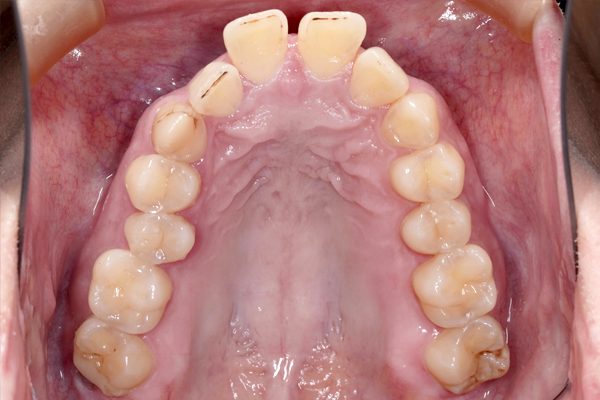

上の歯の比較(咬合面)